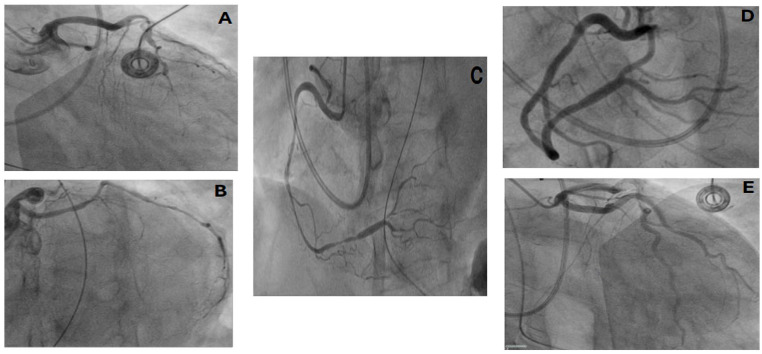

Refractory coronary artery spasm is a challenging condition with many complications, including acute myocardial infarction. We present the case of an elderly woman who developed refractory coronary artery vasospasm requiring extensive hemodynamic support. She had an abnormal electrocardiogram. She was diagnosed with severe coronary artery vasospasm that initially responded to intracoronary nitroglycerin. However, the course was complicated by arrhythmias and cardiogenic shock following an additional episode of vasospasm that required higher concentrations of nitroglycerin. Notably, this case is relatively less documented in women and within the South Bronx population. Refractory coronary artery spasm is a critical condition that can lead to life-threatening outcomes. Prompt and effective treatment is essential, especially for high-risk patients, to prevent cardiac ischemia. Given the significant dangers of delayed or insufficient treatment, it is crucial to manage coronary artery spasms proactively to enhance patient outcomes and avoid severe complications. In addition, this diagnosis should be strongly considered in women, with an emphasis on following guidelines for managing cases of acute myocardial infarction.